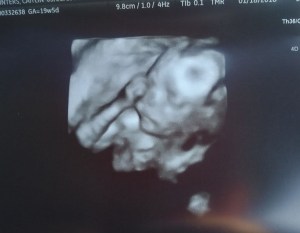

At my 20 week ultrasound I looked at the monitor and immediately said “Hmm, looks like a boy!” I didn’t see anything that would let me know for sure it was just his face! He just looked like a boy to me!